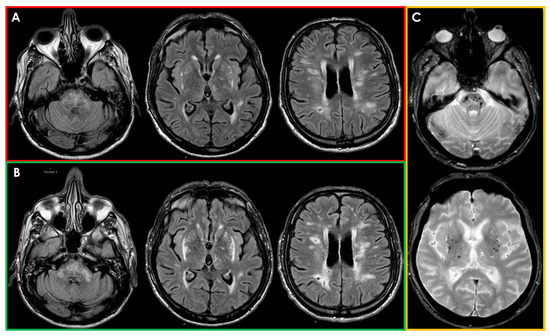

![New Insights in Intracerebral Hemorrhage (Frontiers of Neurology and Neuroscience) [ハードカバー] Toyoda, Kazunori? Anderson, Craig S.; Mayer, Stephan A. Spontaneous intracerebral hemorrhage: a review in](https://images-provider.frontiersin.org/api/ipx/w=1200&f=png/https://www.frontiersin.org/files/Articles/24754/fneur-03-00086-HTML/image_m/fneur-03-00086-g001.jpg)

![New Insights in Intracerebral Hemorrhage (Frontiers of Neurology and Neuroscience) [ハードカバー] Toyoda, Kazunori? Anderson, Craig S.; Mayer, Stephan A. Spontaneous intracerebral hemorrhage: a review in](https://static.cambridge.org/binary/version/id/urn:cambridge.org:id:binary-alt:20181001135430-13989-mediumThumb-04749fig11_1.jpg)

![New Insights in Intracerebral Hemorrhage (Frontiers of Neurology and Neuroscience) [ハードカバー] Toyoda, Kazunori? Anderson, Craig S.; Mayer, Stephan A. Spontaneous intracerebral hemorrhage: a review in](https://ars.els-cdn.com/content/image/1-s2.0-S1474442205701952-gr2.jpg)